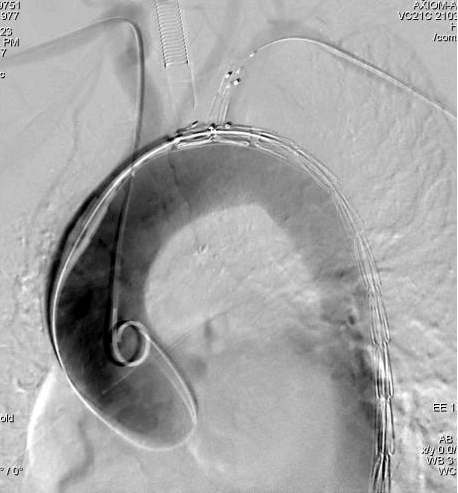

主动脉“修复”介入诊疗技术:

手术中过程图: